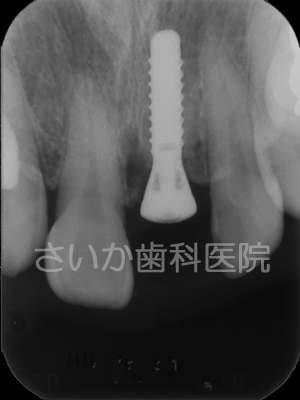

インプラントで対処しました。上は手術後のレントゲン写真です。

冠を被せる前の状態です。チタン製の土台です。

両隣の歯を削らないで治療できること,歯の根があるような状態に戻せることがメリットです。